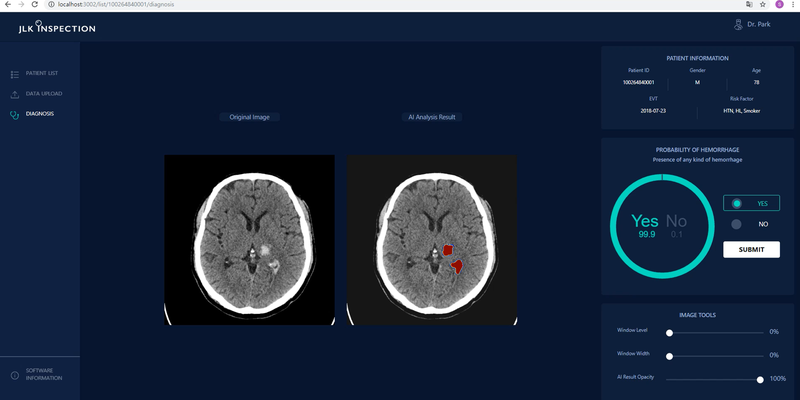

Company: JLK Inc. Product: JBS-04K

Deep learning-assisted detection of intracranial hemorrhage: validation and impact on reader performance

Intracranial hemorrhage (ICH) requires urgent treatment, and accurate and timely diagnosis is essential for improving outcomes. This pivotal clinical trial aimed to validate a deep learning algorithm for ICH detection and assess its clinical utility through a reader performance test.

Retrospective CT scans from patients with and without ICH were collected from a tertiary hospital. Two experts evaluated all scans, with a third expert reviewing disagreements for the final diagnosis. We analyzed the performance of the deep learning algorithm, JLK-ICH, for all cases and ICH subtypes. Additional external validation was performed using a multi-ethnic U.S.

A reader performance study included six non-expert readers who evaluated 800 CT scans, with and without JLK-ICH assistance, following a washout period. ICH presence and five-point scale confidence level for decisions were rated.

A total of 1,370 CT scans were evaluated. The deep learning model showed 98.7% sensitivity (95% confidence interval [CI] 97.8-99.3%), 88.5% specificity (95% CI, 83.6-92.3%), and an area under the receiver operating characteristic curve (AUROC) of 0.936 (95% CI, 0.915-0.957). The model maintained high accuracy across all ICH subtypes, and additional external validation confirmed these results. In the reader performance study, AUROC with JLK-ICH assistance (0.967 [0.953-0.981]) surpassed that without assistance (0.953 [0.938-0.957]; P = 0.009). JLK-ICH particularly improved performance when readers were highly uncertain.

The JLK-ICH algorithm demonstrated high accuracy in detecting all ICH subtypes. Non-expert readers significantly improved diagnostic accuracy for brain CT scans with deep learning assistance.